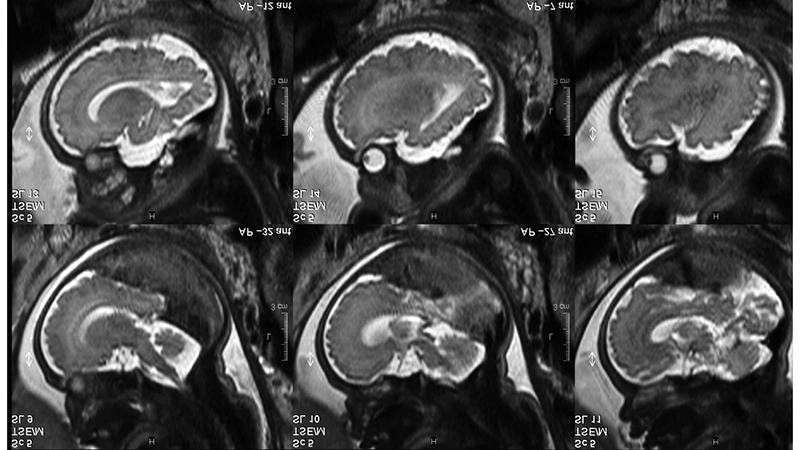

- Καθ´ αυτή δυσπλασία του φλεβώδους κόλπου (Dural Sinus Malformation, DSM) στα νεογνά, στην οποία οι αρτηριοφλεβώδεις επικοινωνίες στο τοίχωμα του φλεβώδους κόλπου είναι αποτέλεσμα της δυσπλασίας του φλεβώδους κόλπου.

- ΑΦ επικοινωνίες στο τοίχωμα του φλεβώδους κόλπου στην βρεφική ηλικία, χωρίς δυσπλαστική διαμόρφωση του φλεβώδους κόλπου.